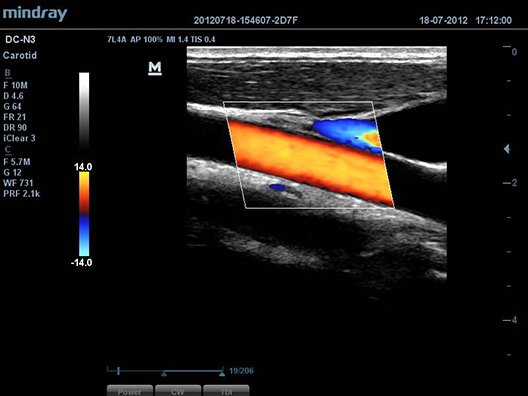

B-SteerTM

–í–∞—à –∏–Ω—Å—Ç—Ä—É–º–µ–Ω—Ç –¥–ª—è –±–æ–ª–µ–µ –≥–ª—É–±–æ–∫–æ–π –±–∏–æ–ø—Å–∏–∏: –æ–±–µ—Å–ø–µ—á–∏–≤–∞–µ—Ç –º–∞–Ω–µ–≤—Ä–∏—Ä–æ–≤–∞–Ω–∏–µ –£–ó-–ª—É—á–∞, —á—Ç–æ–±—ã —É–ª—É—á—à–∏—Ç—å –≤–∏–¥–∏–º–æ—Å—Ç—å –∏–≥–ª—ã, –Ω–µ—Ä–≤–Ω—ã—Ö –≤–æ–ª–æ–∫–æ–Ω –∏ –º–µ–ª–∫–∏—Ö —Å–æ—Å—É–¥–æ–≤.

Auto IMT (–∞–≤—Ç–æ–º–∞—Ç–∏—á–µ—Å–∫–æ–µ –æ–ø—Ä–µ–¥–µ–ª–µ–Ω–∏–µ —Ç–æ–ª—â–∏–Ω—ã –∫–æ–º–ø–ª–µ–∫—Å–∞ –∏–Ω—Ç–∏–º–∞-–º–µ–¥–∏–∞)

–ê–≤—Ç–æ–º–∞—Ç–∏—á–µ—Å–∫–æ–µ –∏–∑–º–µ—Ä–µ–Ω–∏–µ —Ç–æ–ª—â–∏–Ω—ã –ø–µ—Ä–µ–¥–Ω–µ–π –∏ –∑–∞–¥–Ω–µ–π —Å—Ç–µ–Ω–∫–∏, –ø—Ä–µ–¥–æ—Å—Ç–∞–≤–ª—è—é—â–µ–µ —Ç–æ—á–Ω—É—é –∏–Ω—Ñ–æ—Ä–º–∞—Ü–∏—é –æ —Å–æ—Å—Ç–æ—è–Ω–∏–∏ —Å–æ–Ω–Ω–æ–π –∞—Ä—Ç–µ—Ä–∏–∏.